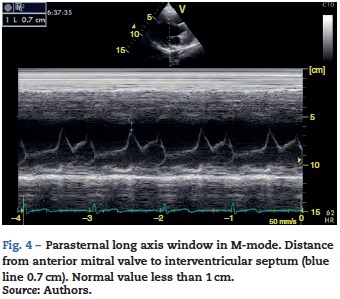

However, this requires 2 planes (apical 4-chamber and 2-chamber) and an advanced calculation that is not always available in these scenarios.45 The M-mode (movement in time) is a more simple method used in the FATE protocol. It allows for the calculation of the shortening fraction (normal greater than 25%) (Fig. 3) and for the approximation of the distance from the anterior mitral valve to the interven-tricular septum (normal less than 1cm) in parasternal long axis (Fig. 4).43 This method should not be considered appropriate in alterations of segmentary contractility.45 The M-mode evaluates systolic function with mitral annular plane systolic excursion (MAPSE) in apical 4-chamber view (normal greater than 15 mm) (Fig. 5).43 Another method is the calculation of systolic volume (normal 45 ± 13 ml) with the Doppler mode and the formula Pi x R2 x VTI (velocity time integral) from the left ventricle outflow tract (LVOT), where R is the radius of the LVOT. The VTI is also indicative of systolic function with 18-20 cm being normal and less than 12 cm considered shock.45